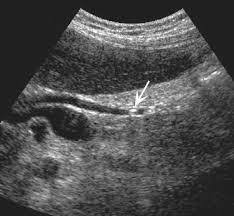

Классической ультразвуковой картиной желчного конкремента являются плотная структура, визуализация только его передней поверхности и акустическая тень на всю ширину камня. При перемене положения тела конкремент смещается. При визуализации конкрементов нужно помнить, что они располагаются в наиболее отлогих местах. Если пациент на исследование пришел самостоятельно, то наиболее вероятным положением конкрементов является область дна, если доставлен на каталке, возможно любое положение камней, в том числе в кармане Гартмана. Для тщательного поиска желательно переменить положение тела пациента: подвижный камень передвинется, фиксированный камень останется на месте. Причинами фиксации может быть ущемление в шейке или формирование местных изменений желчного пузыря в области конкремента. Размеры желчных конкрементов бывают различные. Наименьшие конкременты, которые могут быть визуализированы на современных диагностических приборах, имеют размеры до 2–3 мм. Крупные конкременты могут занимать весь просвет пузыря, последний утрачивает свою работоспособность. Крупные конкременты могут травмировать стенку пузыря, приводить к формированию пролежней, считаются предрасполагающим фактором развития рака желчного пузыря. Мелкие конкременты наиболее опасны, так как могут войти в пузырный проток, диаметр которого около 3 мм, царапнуть стенку и привести к спазму протока. Со спазма протока начинается развитие желчной колики. Определенные трудности представляет диагностика множественных конкрементов, прилегающих друг к другу и заполняющих весь просвет пузыря, желчь в нем отсутствует. В этом случае при ультразвуковом исследовании видна передняя стенка пузыря, за ней определяется зубчатая поверхность переднего ряда камней, дистальнее определяется акустическая тень на всю ширину пузыря. Определить размеры каждого из конкрементов в таком пузыре не представляется возможным, обычно достаточно указать размер наибольшего и наименьшего конкрементов. Иногда возникают сложности при визуализации очень мелких конкрементов, которые имеют маленькие размеры и находятся на дне, или передвигаются в виде маленькой «дорожки камней» с тенями, сливаясь с газосодержащими петлями кишечника у стенки пузыря. Такие конкременты требуют внимания и тщательного полипозиционного исследования. Конкременты могут выходить из желчного пузыря в общий желчный проток, это приводит к увеличению его диаметра. При ультразвуковом исследовании, на фоне желчи, в протоке визуализируется конкремент различных размеров, обычно соответствующих размеру холедоха. Камни холедоха могут не затруднять отток желчи, могут быть вентильными, при определенном повороте приводить к перекрытию просвета, или полностью перекрывать его, приводя к развитию гипертензии желчевыводящих путей и механической желтухе. Конкременты в холедохе могут быть множественными, прилегать друг к другу, иметь фасетчатое строение и полностью закупоривать просвет. Камень может быть ущемленным в дистальной части холедоха и в ампуле большого дуоденального соска, также приводя к гипертензии желчевыводящих путей и развитию холестаза. При ультразвуковом исследовании конкремент в ампуле или дистальной части холедоха лучше визуализируется на срезах головки поджелудочной железы в интрапанкреатической части холедоха. Он лоцируется как акустически плотная структура с тенью, заполняющая просвет расширенного холедоха.